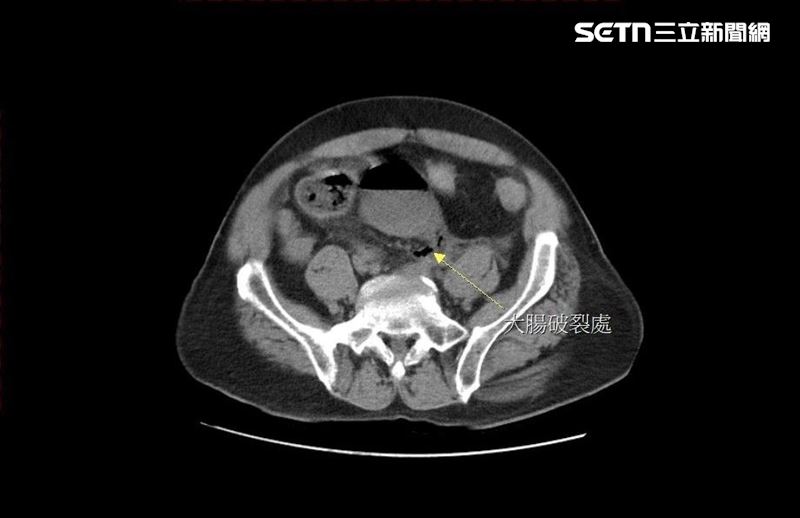

男子因便秘自行灌腸捅破直腸,大量宿便流進腹腔,引發嚴重腹膜炎。(圖/大千醫院提供)

院方緊急安排電腦斷層掃描發現,黃男的直腸上端處出現巨大破洞,已有糞水從破洞流入腹腔,院方立即進行腹腔鏡手術,在直腸上端靠近乙狀結腸的轉彎處,找到一個直徑2公分的破洞,研判是黃男太用力灌腸,造成腸道破損,大量宿便流進腹腔,引發嚴重腹膜炎,幸好及時手術治療,保住性命。